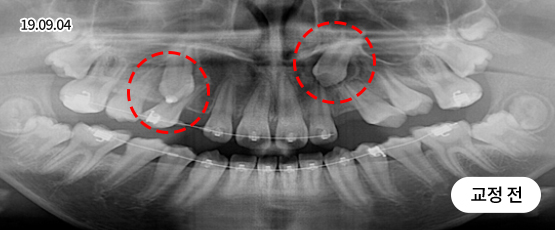

매복치 Solution

매복치는 잇몸 속에서 인접 치아에 손상을 줄 수 있어

치아 견인을 통해 제자리를 찾아주어야 정상적으로 치아가 자리 잡을 수 있습니다.

* 치근흡수, 잇몸퇴축 등 부작용이 발생할 수 있습니다.